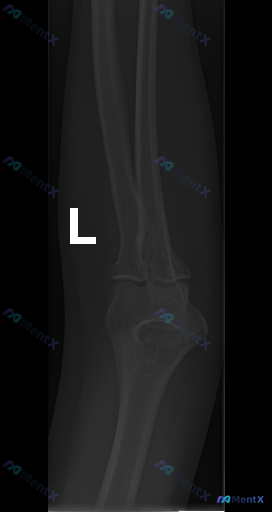

整理了一份左肘关节侧位X光片的分析资料,觉得这种场景挺常见的,发出来大家讨论一下。 当前情况: - 影像:左肘侧位X光片(只有侧位) - 影像报告结论:各主要骨性结构皮质连续,关节对位良好,未见明显骨折脱位,脂肪垫无抬高,软组织无明显肿胀,骨骺已闭合。 - 矛盾点:有临床先验提示「存在异常」(但没给...

整理到一个肘部外伤的影像病例,先不放完整流程,只看侧位X光的征象描述,大家第一眼会先注意到什么? 影像信息:成人肘部侧位片,骨骺已闭合。 可见表现: 1. 尺骨近端(包括鹰嘴、冠突)与肱骨滑车对应关系完全丧失,尺骨及桡骨相对于肱骨向后上方明显移位 2. 尺骨冠突边缘可见骨质断裂线 3. 关节周围软组...